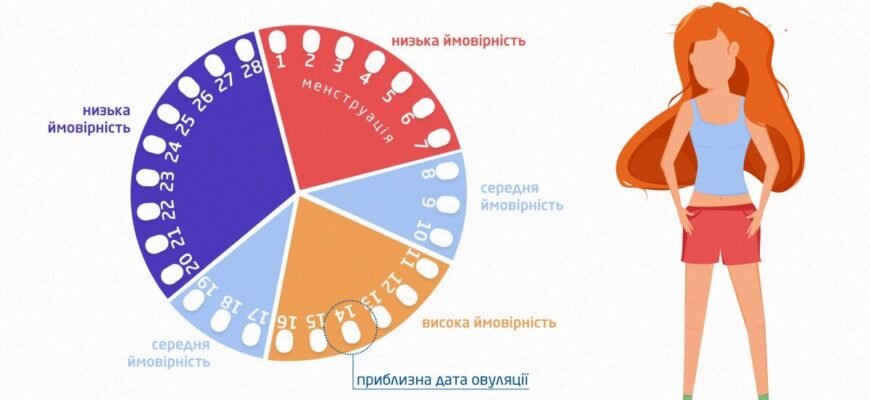

Чи можна завагітніти, коли є жовте тіло? Питання «чи можна завагітніти, коли є жовте тіло» турбує багатьох жінок, які уважно стежать за своїм циклом та

Чи можна завагітніти в останній день місячних? Розбираємося в деталях Чи можна завагітніти в останній день місячних? Питання, яке хвилює багатьох жінок